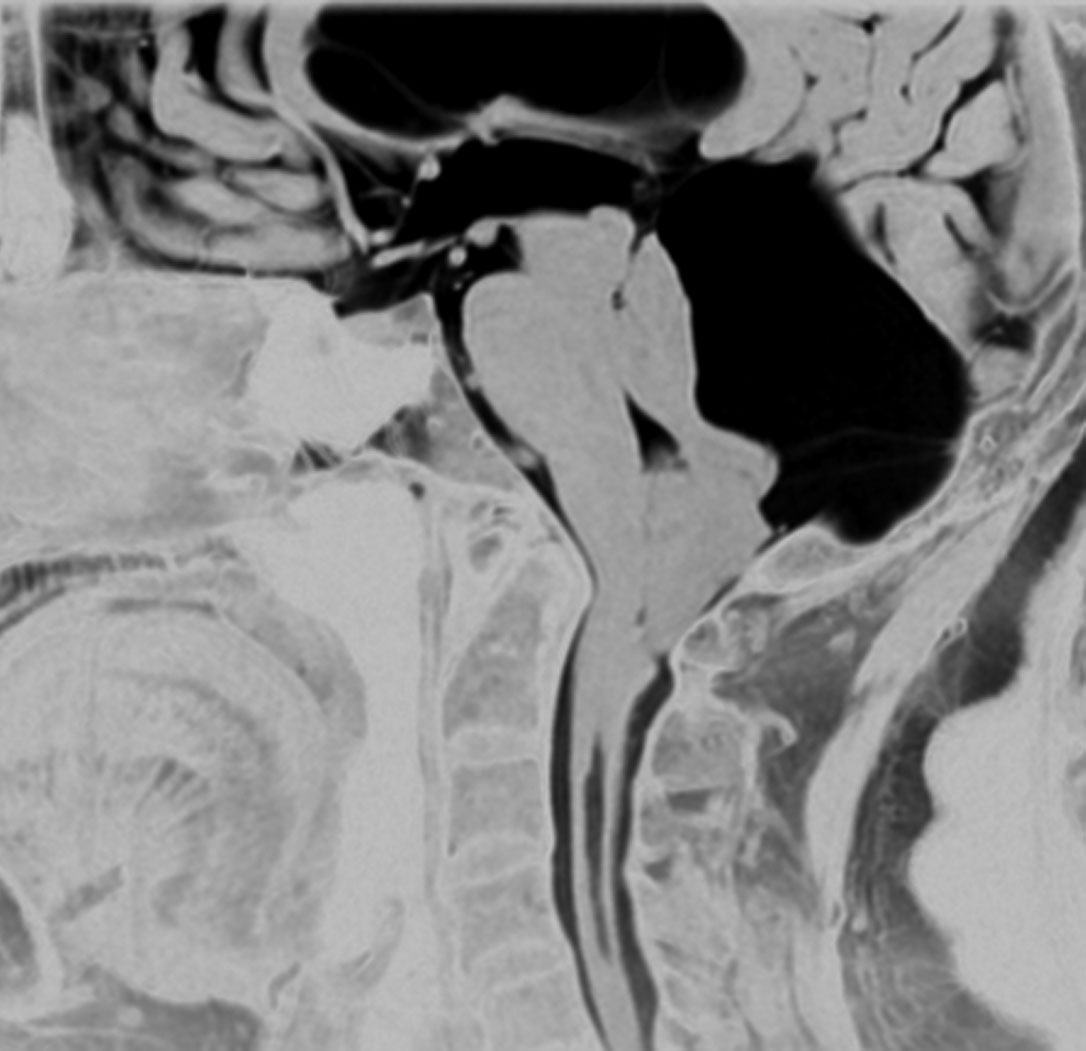

鞍上部クモ膜のう胞

20歳代の女性の無症候性のものです。水色に塗ったのがクモ膜のう胞です。特徴的なのは,下垂体柄が長〜く伸びて細くなっていることです,でも下垂体障害はでません。珍しいことですが,松果体のう胞(黄色の部分)が合併しています。治療の必要がないものです。